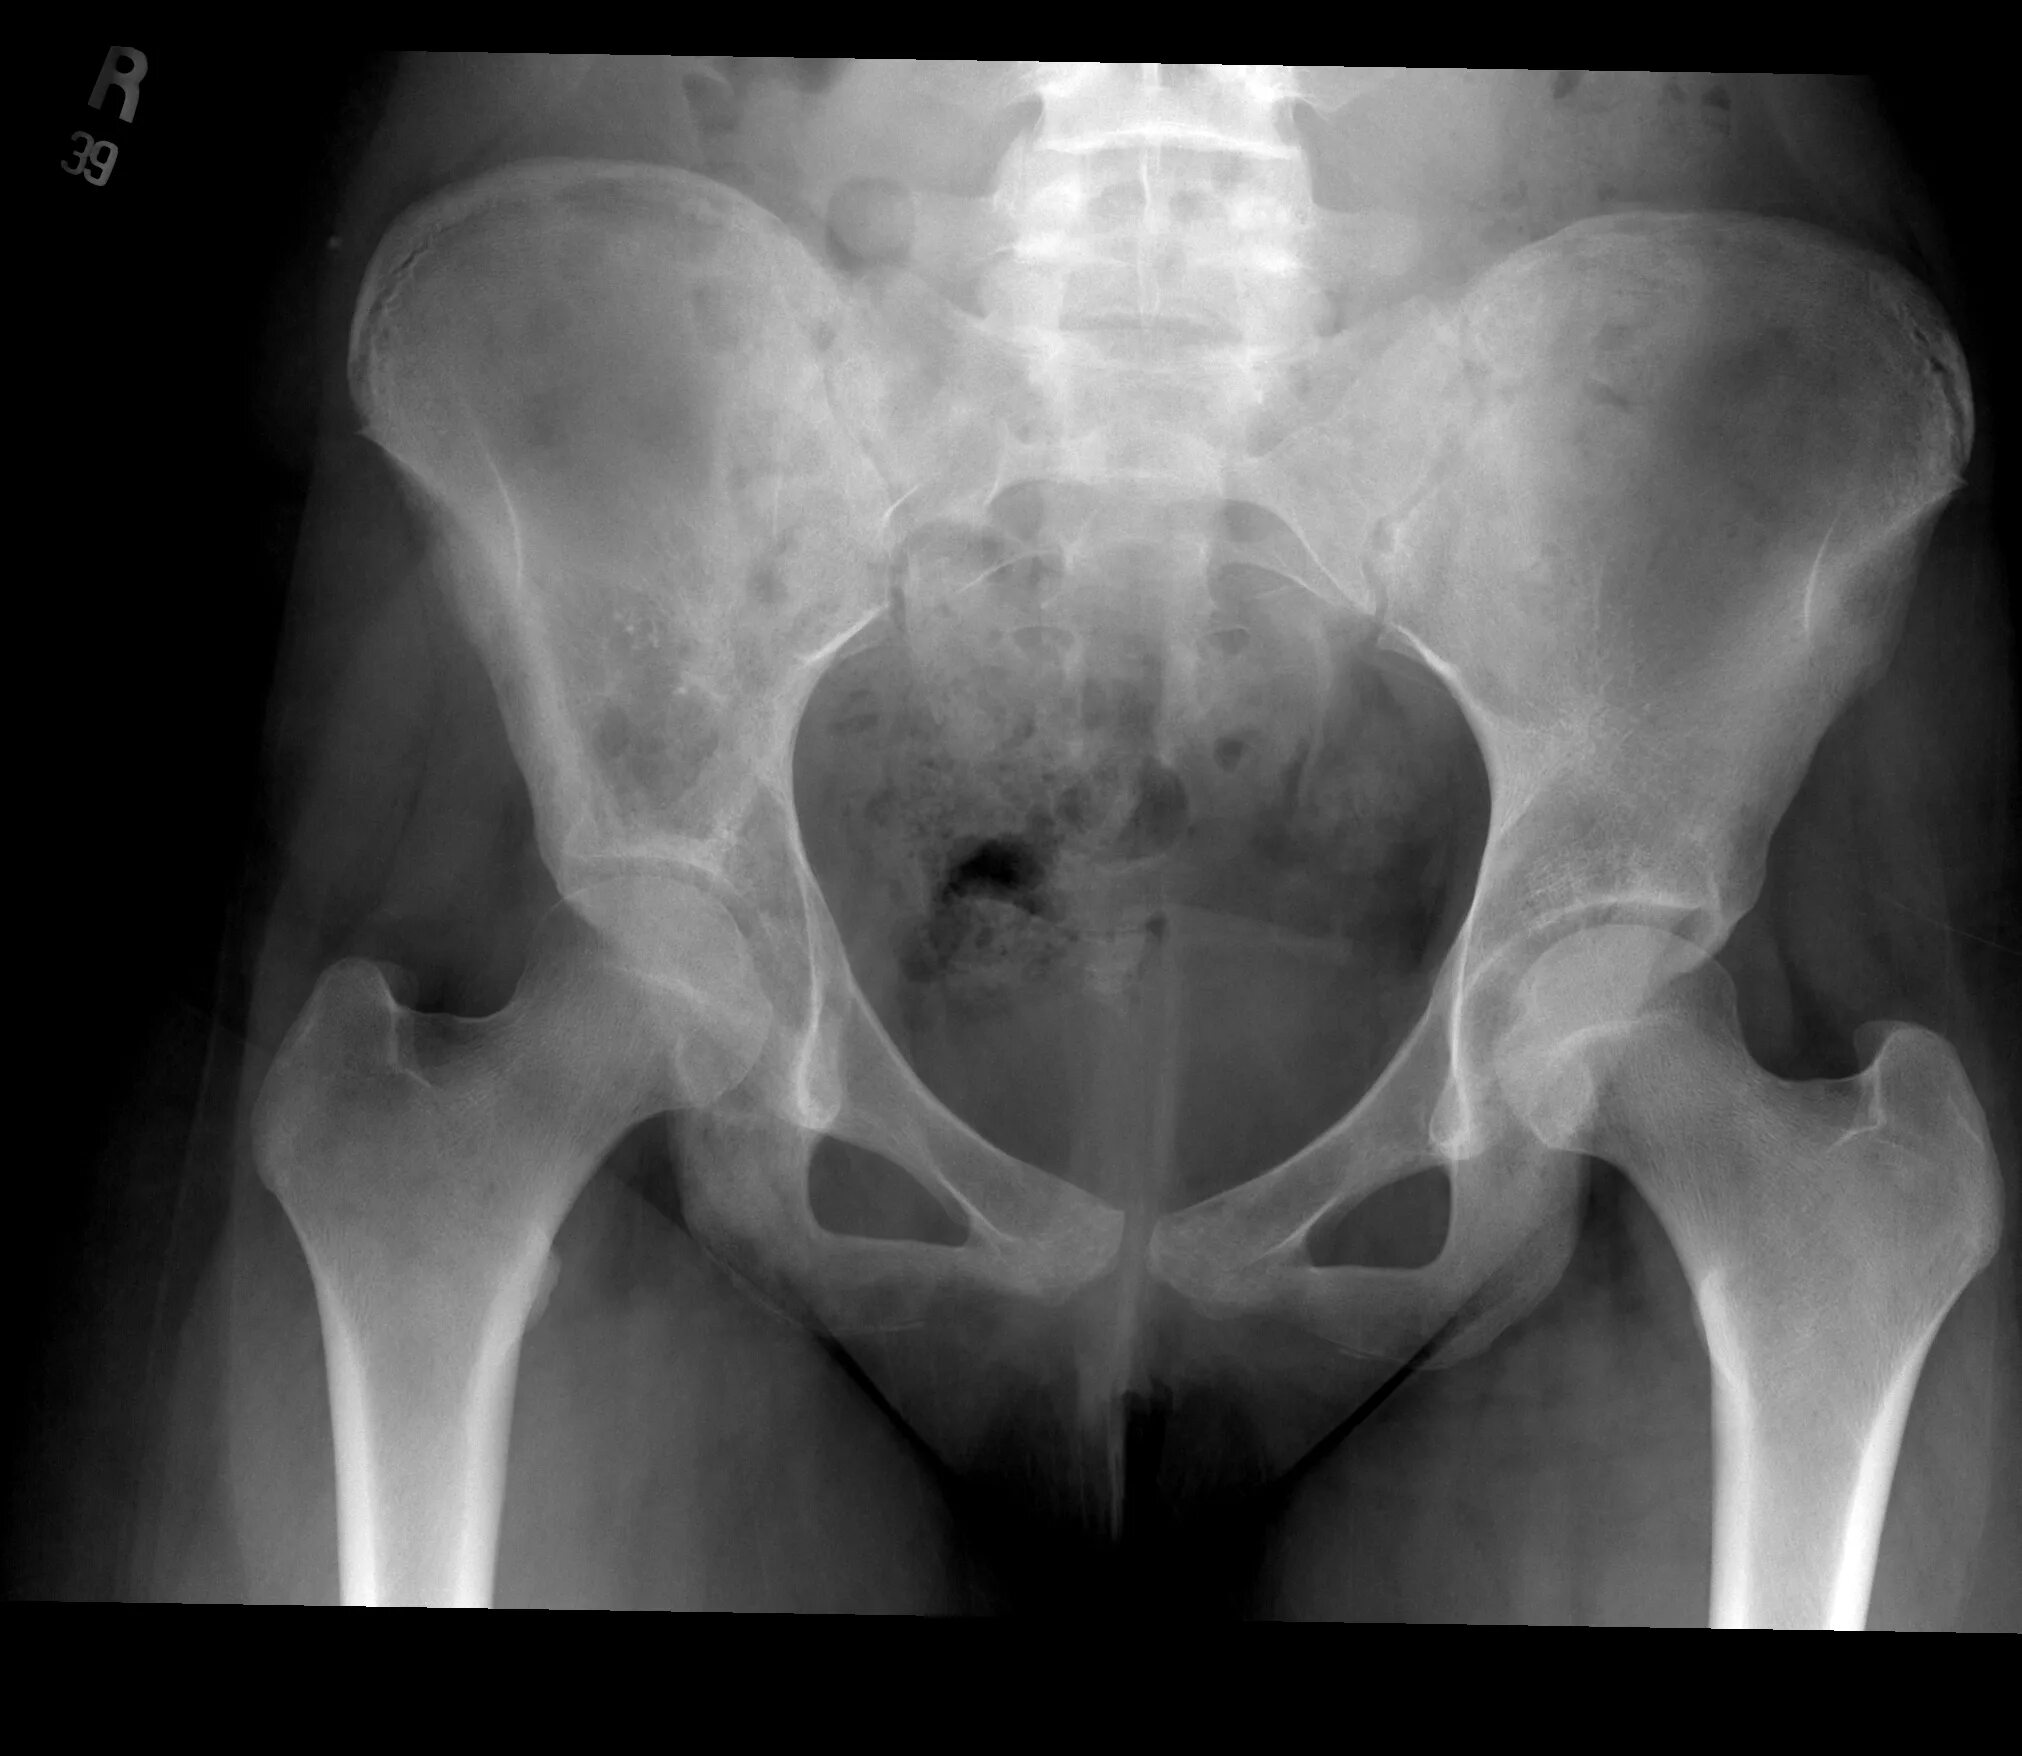

Метастазы в тазобедренном